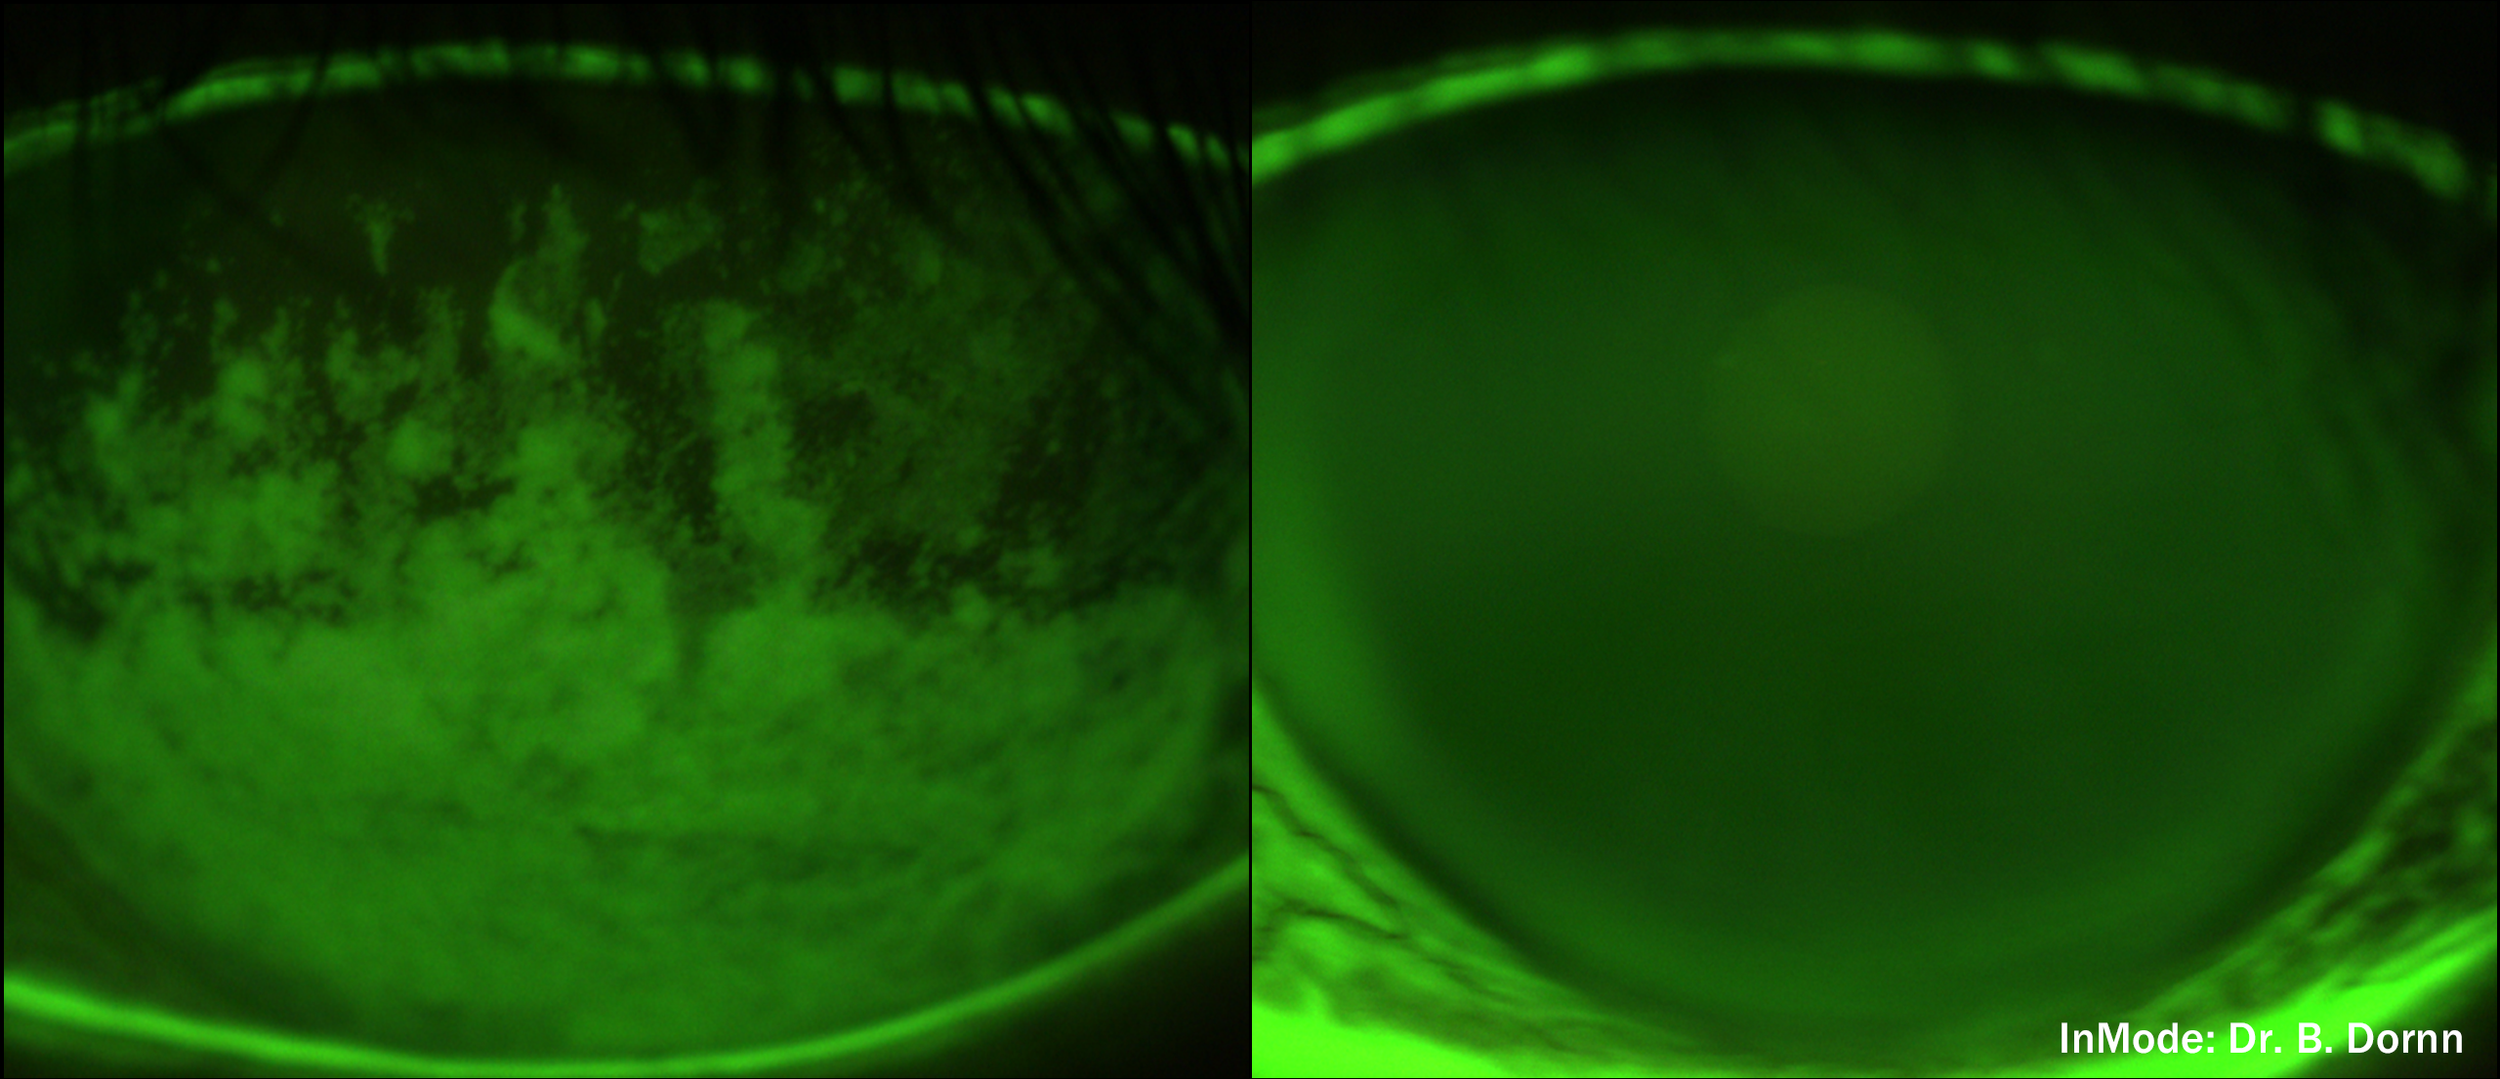

Before & After